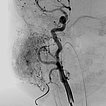

In der digitalen Subtraktionsangiographie (DSA) nach Injektion in die rechte Arteria carotis communis zeigt sich das Hämangiom wie erwartet vor allem aus der Arteria carotis externa versorgt.